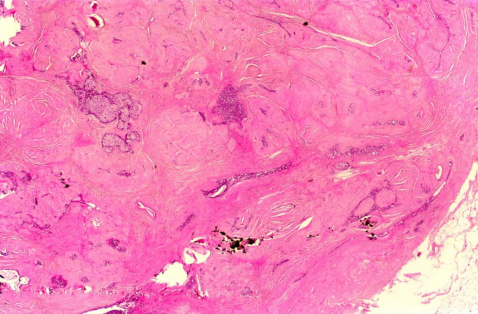

Tartışılması gereken bir durum da tarama mammografilerinin meme kanserine bağlı ölüm oranının azaltılmasındaki maliyet etkinliğidir. Kırk yaşından başlayarak 79 yaşına kadar yapılan tarama mammografisinin her sağkalınan yıl başına maliyeti 18.800 dolar olarak bulunmuştur. Bu rakam serviks kanseri ve osteoporoz taramalarının aynı şartlardaki maliyeti ile karşılaştırıldığında rakamlar yaklaşık çıkmaktadır. Bu rakam hormon replasman tedavileri, kalp transplantasyonu, hemodiyaliz, koroner arter cerrahisi maliyetlerinden daha azdır23. Öte yandan mammografi ile erken evrede saptanan lezyonların tedavi giderleri daha az olmakta, hastaların adjuvan tedavilerine ait maliyetler düşmekte, iş gücü kaybı azalmakta, hastalık nükslerine ait maliyetler de düşmektedir. Buna bir örnek olarak lokal ileri evre meme kanserlerini verebiliriz. Lokal ileri evre meme kanserleri evre II (T2N1M0, T3N0M0) ve evre IIIA,B,C’yi içermektedir. Maalesef ülkemizde tüm çabalara karşın lokal ileri evre meme

kanseri oranı %15-20 gibi ciddi bir oranda görülmekte, bu da tedavi maliyeti ve sağkalım başarısını olumsuz etkilemektedir. (Resim 1)

Resim 1. Genellikle Evre 3 B olarak değerlendirilen lokal ileri evre meme kanseri